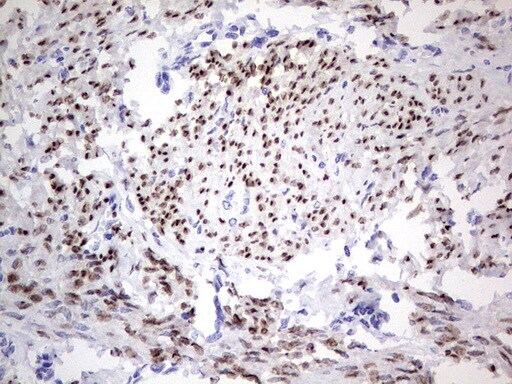

- Submitted by

- Invitrogen Antibodies (provider)

- Main image

- Experimental details

- Immunohistochemical staining of paraffin-embedded Adenocarcinoma of Human endometrium tissue using anti-PGR mouse monoclonal antibody. (Heat-induced epitope retrieval by 1 mM EDTA in 10mM Tris, pH8.5, 120°C for 3min, TA805108)